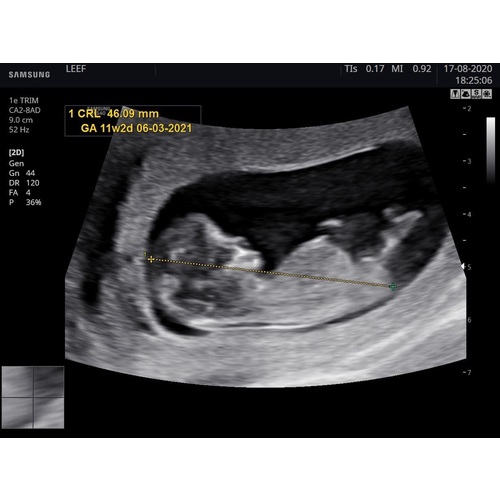

12.3 weken wat denken jullie ? De verloskundige dacht aan de nub een meisje te zien ik denk zelf een jongen

Gister echo gemaakt met 13+3 weken. Wat zal het worden volgens de nub-theorie? Ben zo benieuwd maar zie het zelf niet.